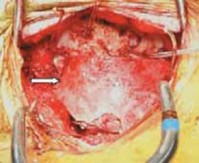

1. An oblique incision overlying the posterior rib allows for adequate exposure.3

1. The muscle fibers are separated and dissection is carried down to the periosteum of the rib.

2. Adequate rib is exposed and cut.

1. The size of the rib graft is greater than the area to be fused because part of the rib is used as morcelized graft.

2. Using a rib cutter, the graft is cut distally and proximally and removed (

TECH FIG 2A

).

3. Irrigation fluid is placed in the surgical site and positive pressure applied to check for pleural leaks.

4. If a pleural tear is detected, air can be removed from the chest cavity by using a red rubber tube and suction.

5. A larger leak may require placement of a thoracostomy drainage tube.

1. In all patients, a chest radiograph should be taken after rib harvest to rule out pneumothorax.

6. Two full-thickness structural grafts are prepared to fit the arthrodesis site.

7. The rib grafts can span large defects and fit nicely into large or abnormally shaped skull, and we find this best for young infants.

8. 16- or 18-gauge wire is looped through the burr holes on each side of the midline (see TECH FIG 1C).

1. The burr holes are drilled and aligned similarly to the ones described for the iliac graft technique.

1. There is no need to create a groove at the base of the occiput.

54. Braided cable or no. 5 Mersilene sutures may be used instead of wire.

1. With Mersilene sutures there is a reduced risk of cutting out in thin bone of poor quality.

55. After this, purchase of two wires is made to the posterior elements of most caudal vertebra on each side of the midline by sublaminar wiring.

56. Suitable grafts on either side are then secured to the occiput and lamina of the most caudal vertebra by wires.

1. The stability of the grafts is checked under radiographic control and the wires are then crimped and cut (

TECH FIG 2B,C

57. Adjustments are made by flexion–extension of the halo frame, contouring of the graft, and appropriate tightening of the wire.

1. Intraoperative radiographs are obtained to confirm acceptable reduction, alignment, and placement of the graft.